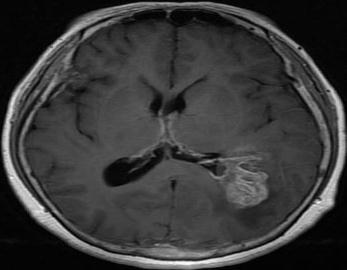

Fig - 1 : Flowchartofproposedmethod TheDatasetofbrainwithtumor: TheDatasetofbrainwithouttumor:

Infirststagewesuccessfullyconvertedtheinputimage(an OpenCV image) to grayscale using edge detection after applying pre-processing. Edge-based segmentation on an imageclassifiespixelsasedgeornon-edgedependingonthe filteroutput.Inregion-basedsegmentation,theimagewas subjected to regional maxima in order to group adjacent pixelswithsimilarvalues.TheCNNmodelwastrainedand testedbeforetheK-meanstechniquewasusedtoidentifythe regionofinterest(ROI),whichwasthenexaminedforthe presenceofatumor.

Fig - 2 : ImagePreprocessing OriginalImage CroppedImage Fig - 3:CNNmodelarchitecture Fig - 4:Trainingmodel